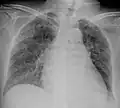

| Chest X ray showing miliary tuberculosis | |

Miliary tuberculosis is a form of tuberculosis that is characterized by a wide dissemination into the human body and by the tiny size of the lesions (1–5 mm). Its name comes from a distinctive pattern seen on a chest radiograph of many tiny spots distributed throughout the lung fields with the appearance similar to millet seeds—thus the term "miliary" tuberculosis. Miliary TB may infect any number of organs, including the lungs, liver, and spleen.[2] Miliary tuberculosis is present in about 2% of all reported cases of tuberculosis and accounts for up to 20% of all extra-pulmonary tuberculosis cases.[3]